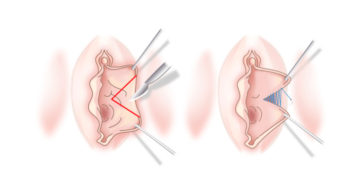

Пластика половых губ: что такое лабиопластика, фото до и после коррекции Не секрет, что представительницы…